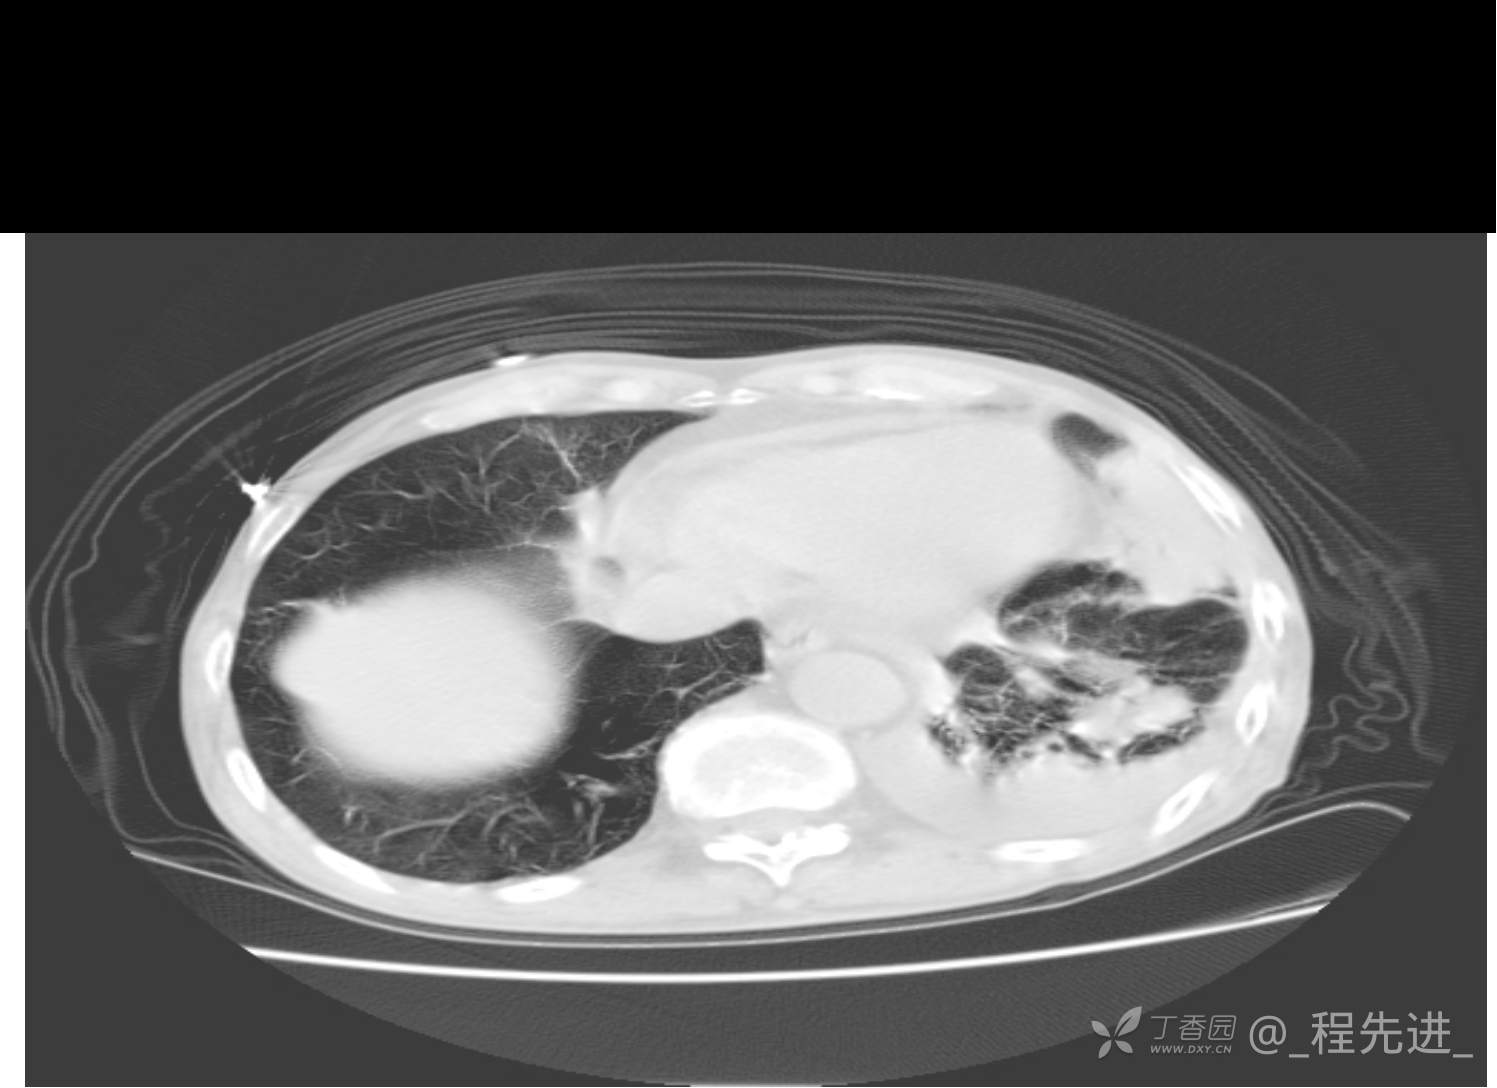

患者性别:男

患者年龄:81岁

简要病史:反复咳嗽、咳痰20余年,加重1周。两肺呼吸音低,可闻及散在干湿啰音。